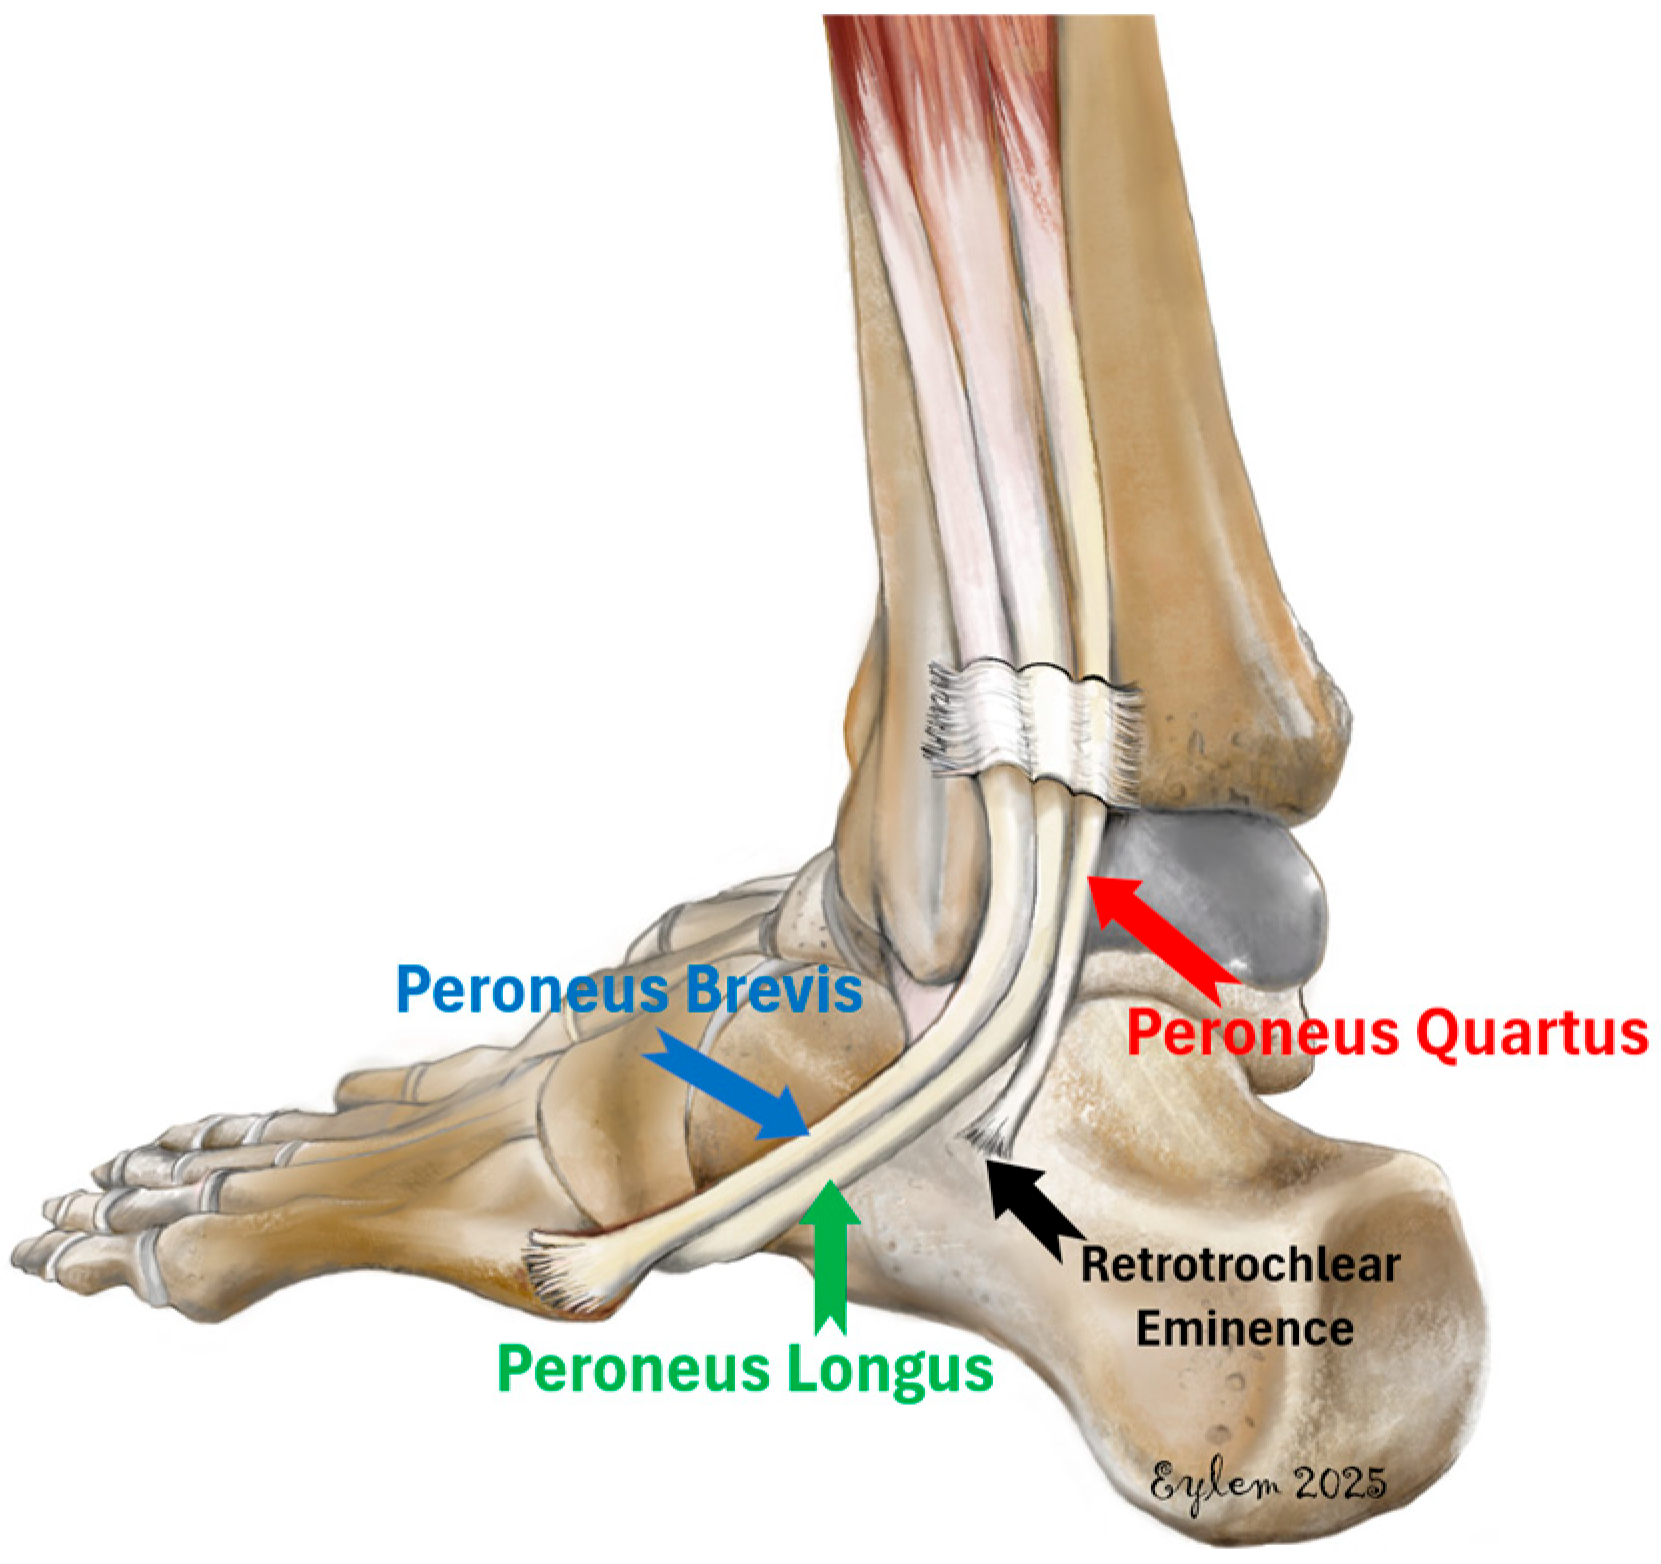

1. Introduction

2.3. Assessment of the Peroneus Quartus Muscle and Peroneal Pathologies

2.4. Definitions of Peroneal Tendon Pathologies